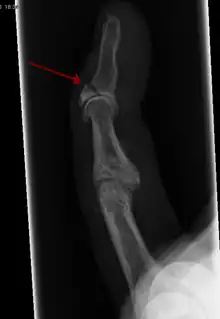

Patterns

| Photo | Type | Description | Causes | Effects |

|---|---|---|---|---|

![]() In the fingertip. More images |

Linear fracture | Parallel to the bone's long axis | ||